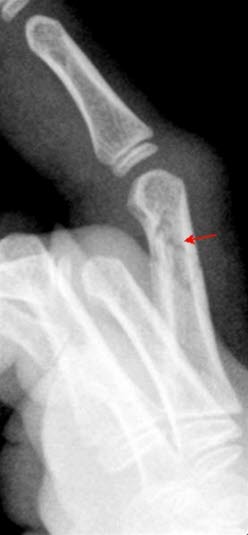

Phalanx-fraktur side

Fraktur i 3. fingers proksimale falang uten feilstilling